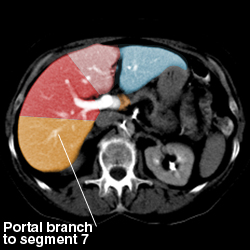

Liver anatomy

Segmental Anatomy of Liver